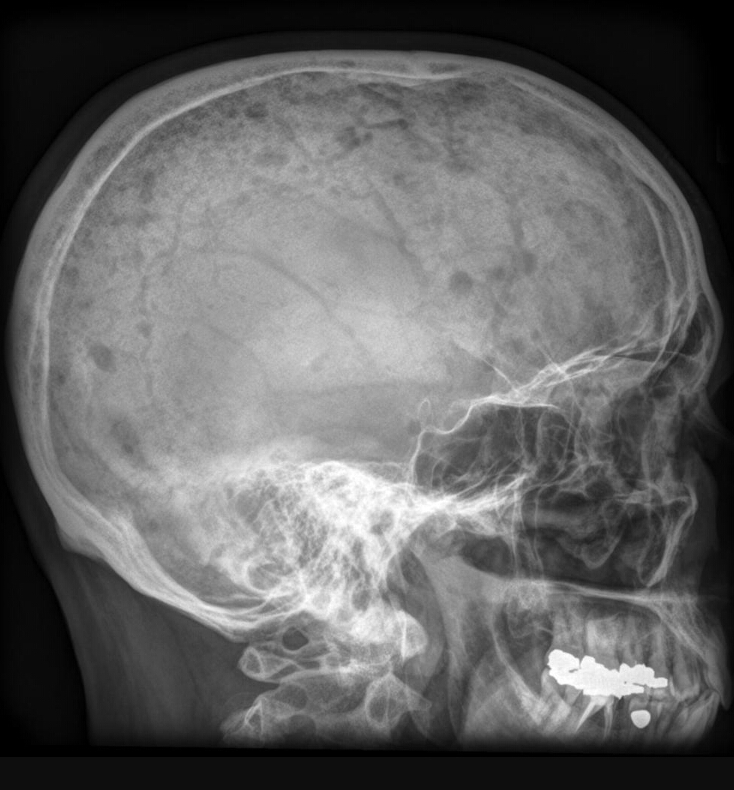

Findings? Diagnosis?

Well circumscribed round extremely dense lesion around 2cm in size in the frontal bone

Osteoma